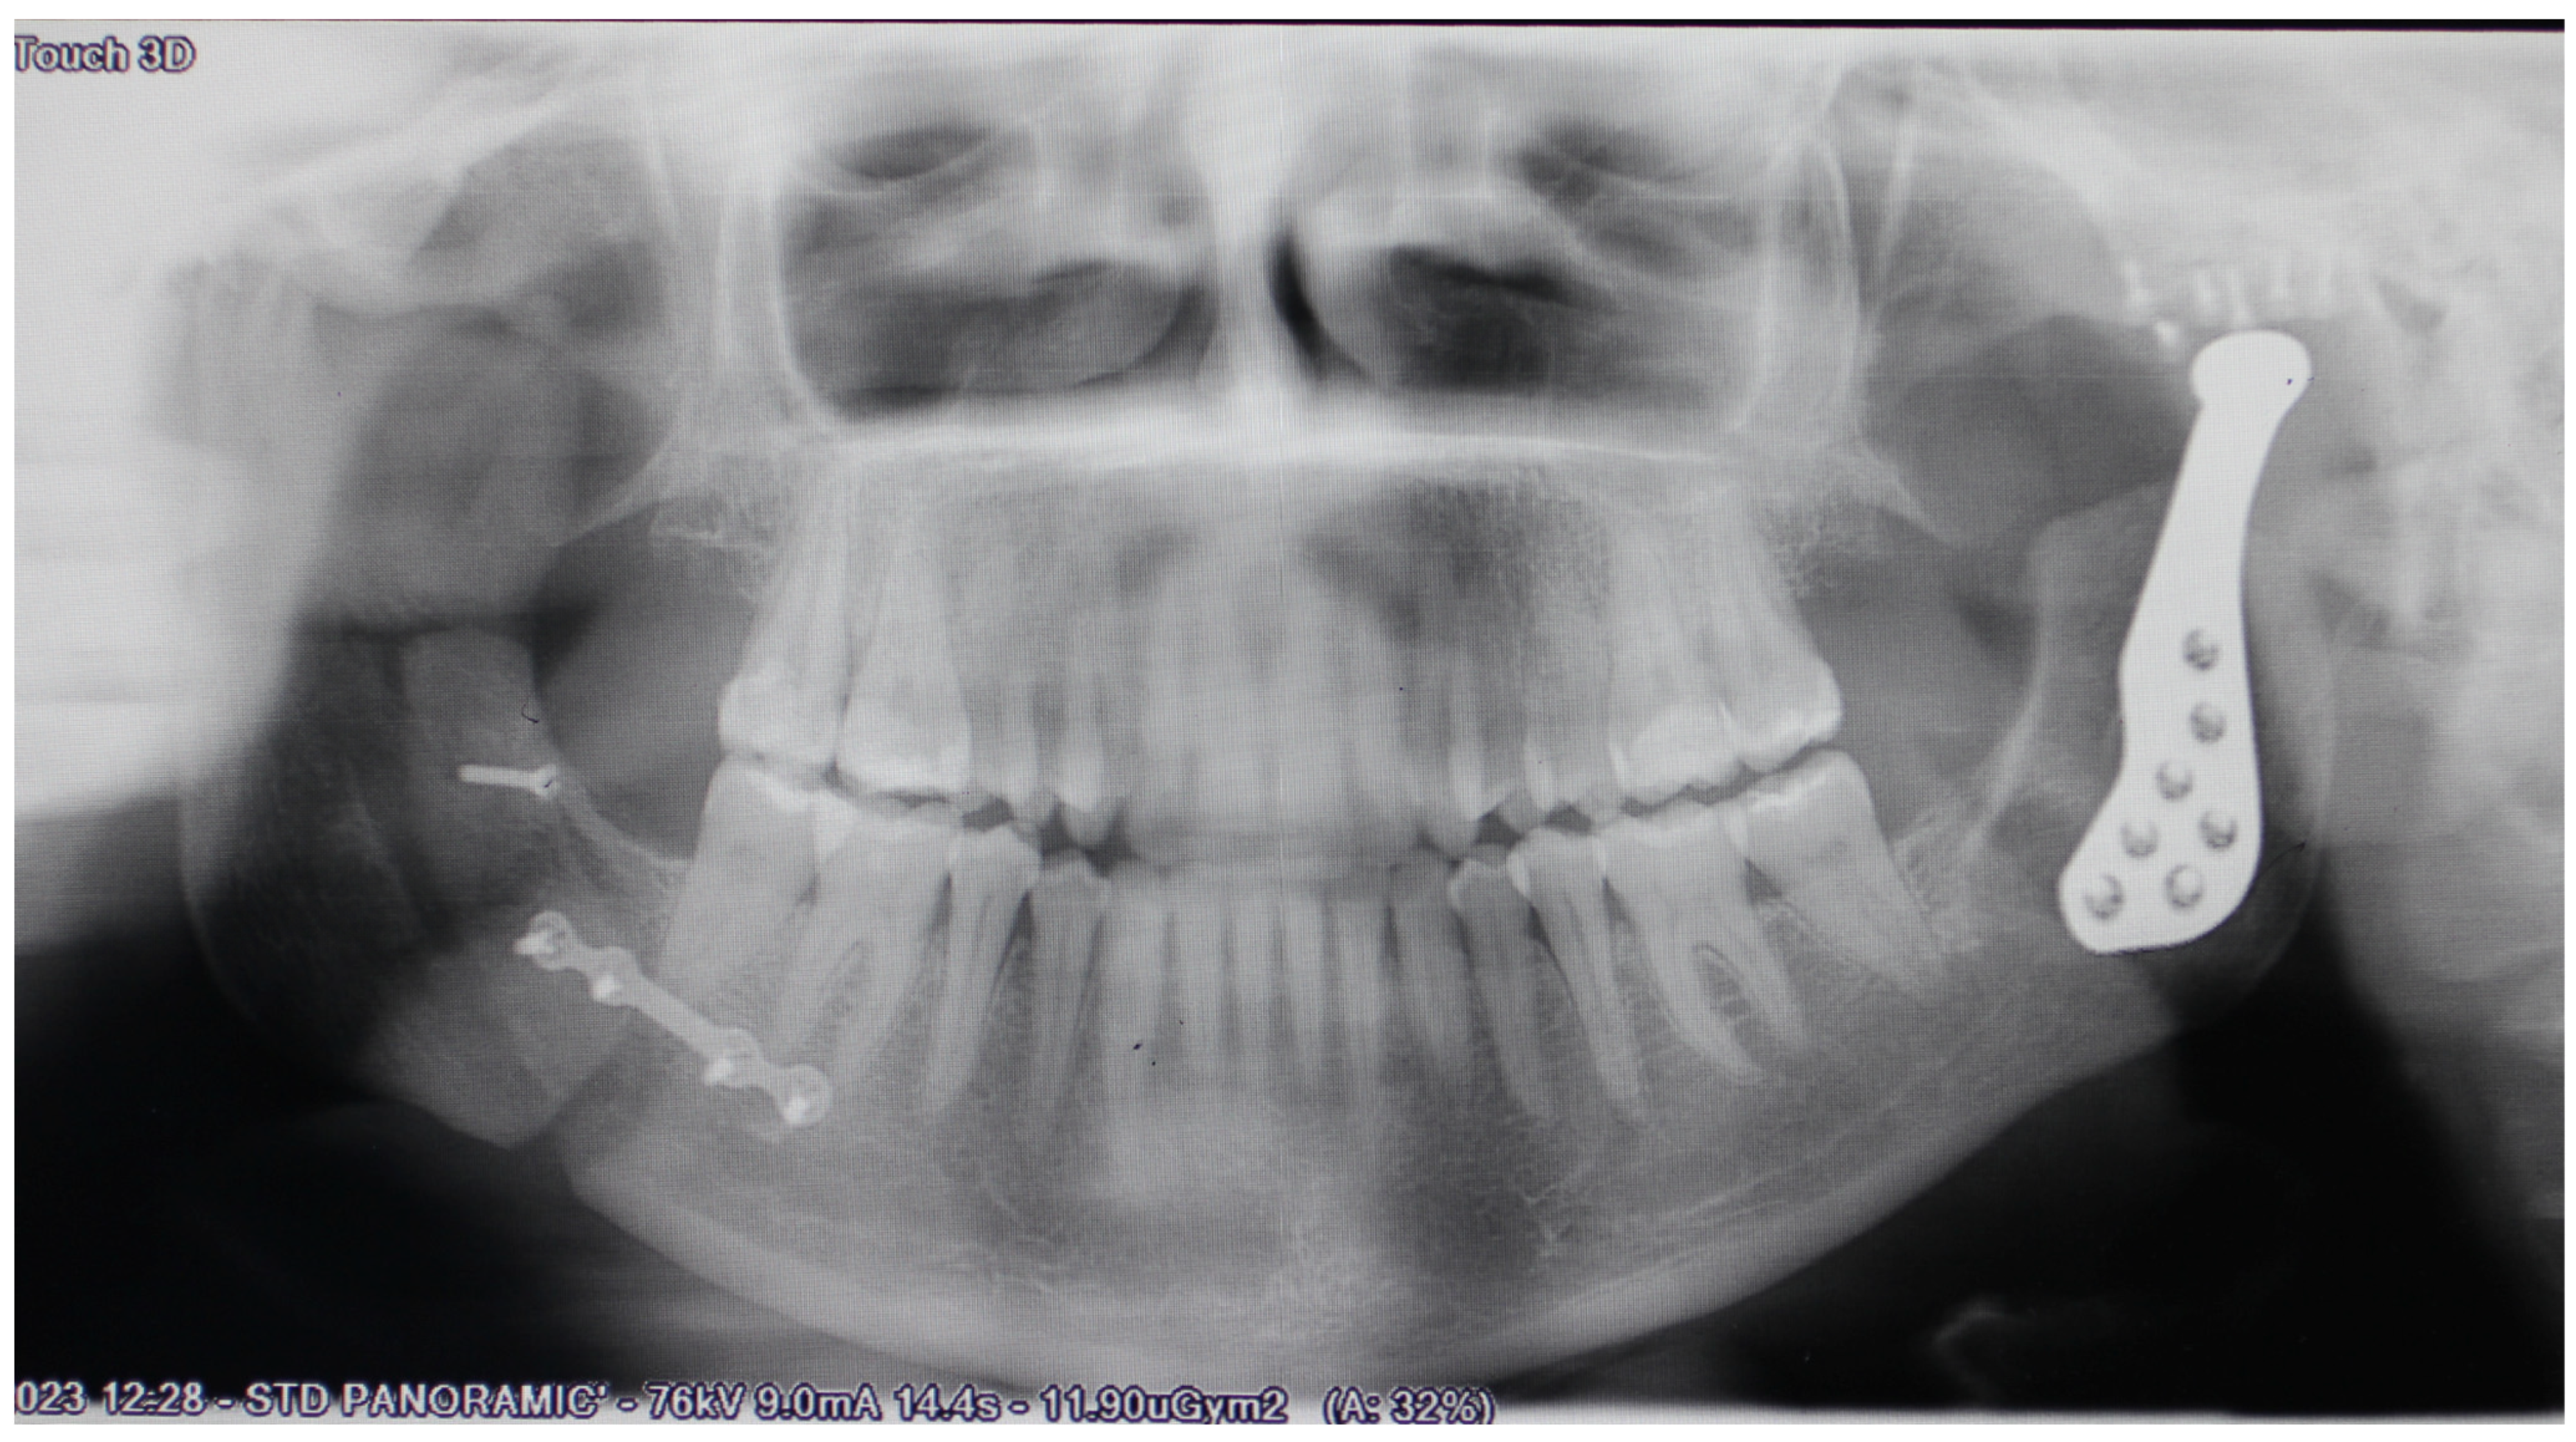

2.2. Preoperative Planning

2.3. Surgical Procedure